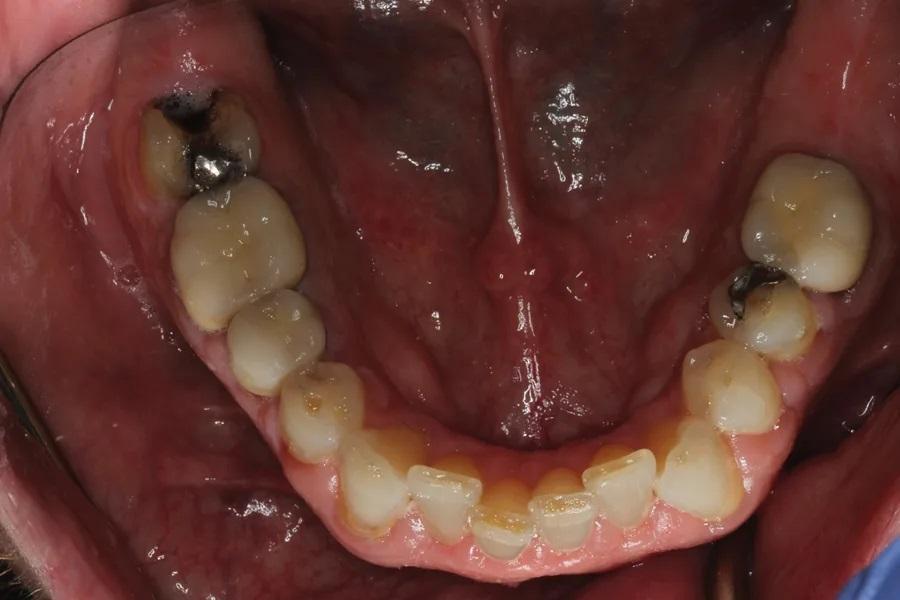

Биомеханика: Кариозные поражения: 1.6–1.3, 2.4, 2.5, 3.7, 3.5, 3.4, 4.4. Крупные реставрации: 1.7–1.3, 2.5–2.7, 3.7–3.5, 4.5, 4.6. Три зуба под коронками; эндодонтическое лечение ранее — 3.6 и 3.5. Зуб 3.7 — значительная утрата тканей. На передних зубах — умеренно-тяжелая атриция и эрозия. Ряд реставраций на 1.4, 2.3, 2.4, 3.7 — неудовлетворительное состояние/неудачные (Фото 5 и Фото 6).

Фото 6. Окклюзионный вид нижнечелюстной дуги до лечения. Обратите внимание на умеренное истирание передних зубов и сломанный зуб 3.7.